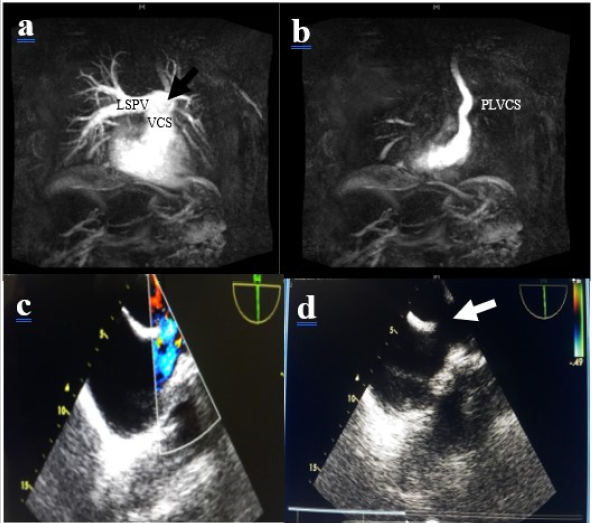

Mini Case Study

A Silent but Impressive Left Ventricular Pseudoaneurysm: A Case Report

Benzha Mohamed Yassine, Pace Nathalie, Liu Yihua, Scadi Soukaina and Juan Pablo Maureira. 10(2): 36-38.